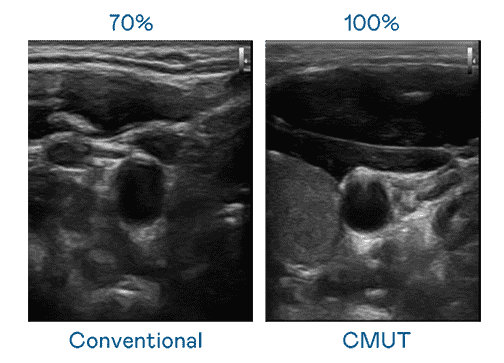

CMUT 技术是一种用电容式微机电元件来产生超音波讯号的技术。。。与传统 PZT 压电式技术相比,,,,CMUT 频宽增加 30%,,,更宽频的超音波讯号让影像解析度大幅提升,,,是实现高影像品质医疗超音波扫描、、、促进精准医疗发展的关键技术。。

大频宽带来超清晰影像

超音波影像的解析度高低,,首先取决于探头能发出的讯号频宽。。。尊龙集团 CMUT 可提供高清晰的超音波讯号,,提供高频宽、、、高灵敏度、、、、影像纹理细节更高的超音波影像,,,协助医护人员缩短影像判读时间及利用精准的医疗影像进行诊断。。。。